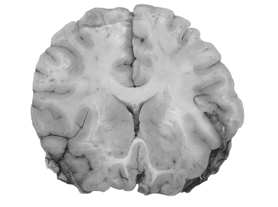

г) Напомню, что миелиновые оболочки аксонов ускоряют перемещение вдоль них потенциала действия. Цвет миелина практически белый, поэтому нейронные тракты в мозге выглядят светлыми. Из-за этого их часто называют «белое вещество».

д) Несложно увидеть, что белое вещество и нервные волокна занимают значительную часть мозга: все его отделы посылают информацию в другие участки, зачастую весьма удаленные[544].